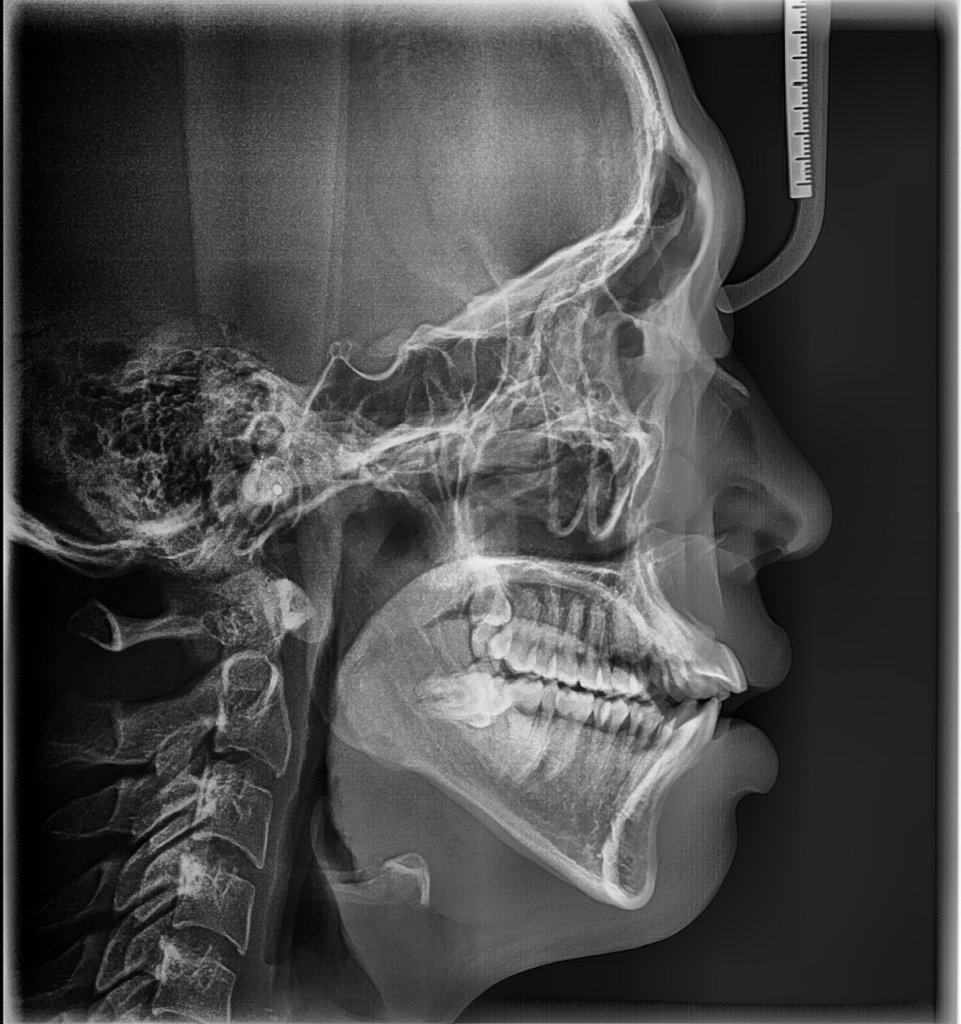

첫번째 사진은 교정 시작 전이고

• 1번 째 사진